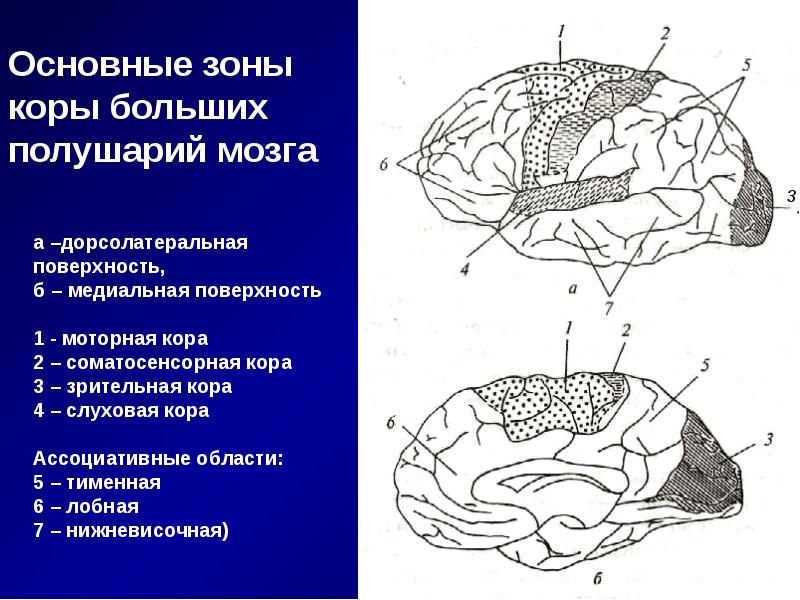

Схема чувствительных зон новой коры мозга